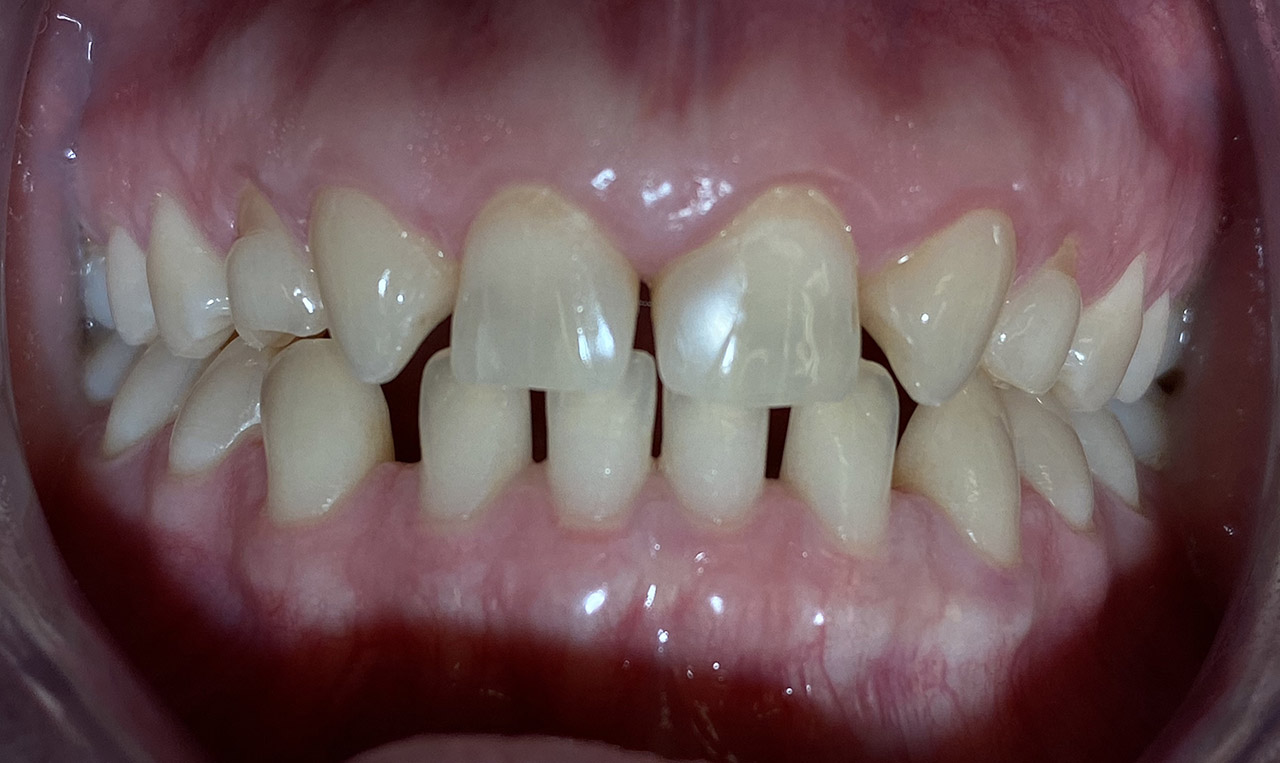

Ästhetische Zahnheilkunde / der komplexe Fall

Aplasien/Nichtanlagen, dadurch bleibende Milchzähne, Diasteme/Zahnlücken,

Bleaching/Bleichen, Positionierung der Zähne/Kieferorthopädie (Dr. Maija Eltz), Verblendung mit Veneers/Keramikschalen.

Vorher Nachher